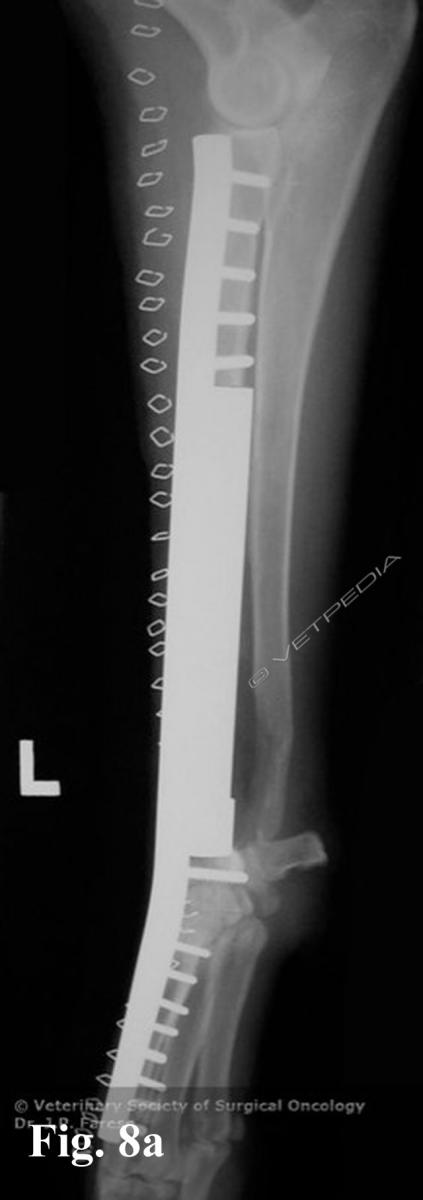

{{/_source.additionalInfo}}L'osteosarcoma è un tumore che può svilupparsi sia nel cane che nel gatto.Nel cane rappresenta l’85-98% dei tumori ossei in questa specie animale (Liptak et al., 2004b; Dernell et al., 2007). Sono più frequenti le localizzazioni appendicolari (75%) ma può anche svilupparsi a carico dello scheletro assiale (24%) e occasionalmente in sedi e